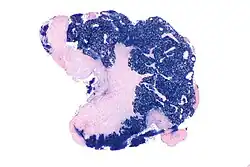

Nasopharyngeal carcinoma, also known as nasopharyngeal cancer, is classified as a malignant neoplasm, or cancer, arising from the mucosal epithelium of the nasopharynx, most often within the lateral nasopharyngeal recess or fossa of Rosenmüller (a recess behind the entrance of the eustachian tube opening). The World Health Organization classifies nasopharyngeal carcinoma in three types, in order of frequency: Non-keratinizing squamous cell carcinoma; keratinizing squamous cell carcinoma; and basaloid squamous cell carcinoma.[15] The tumor must show evidence of squamous differentiation; with the non-keratinizing type (also known as lymphoepithelioma), the tumor is most strongly associated with Epstein–Barr virus infection of the cancerous cells.[16]